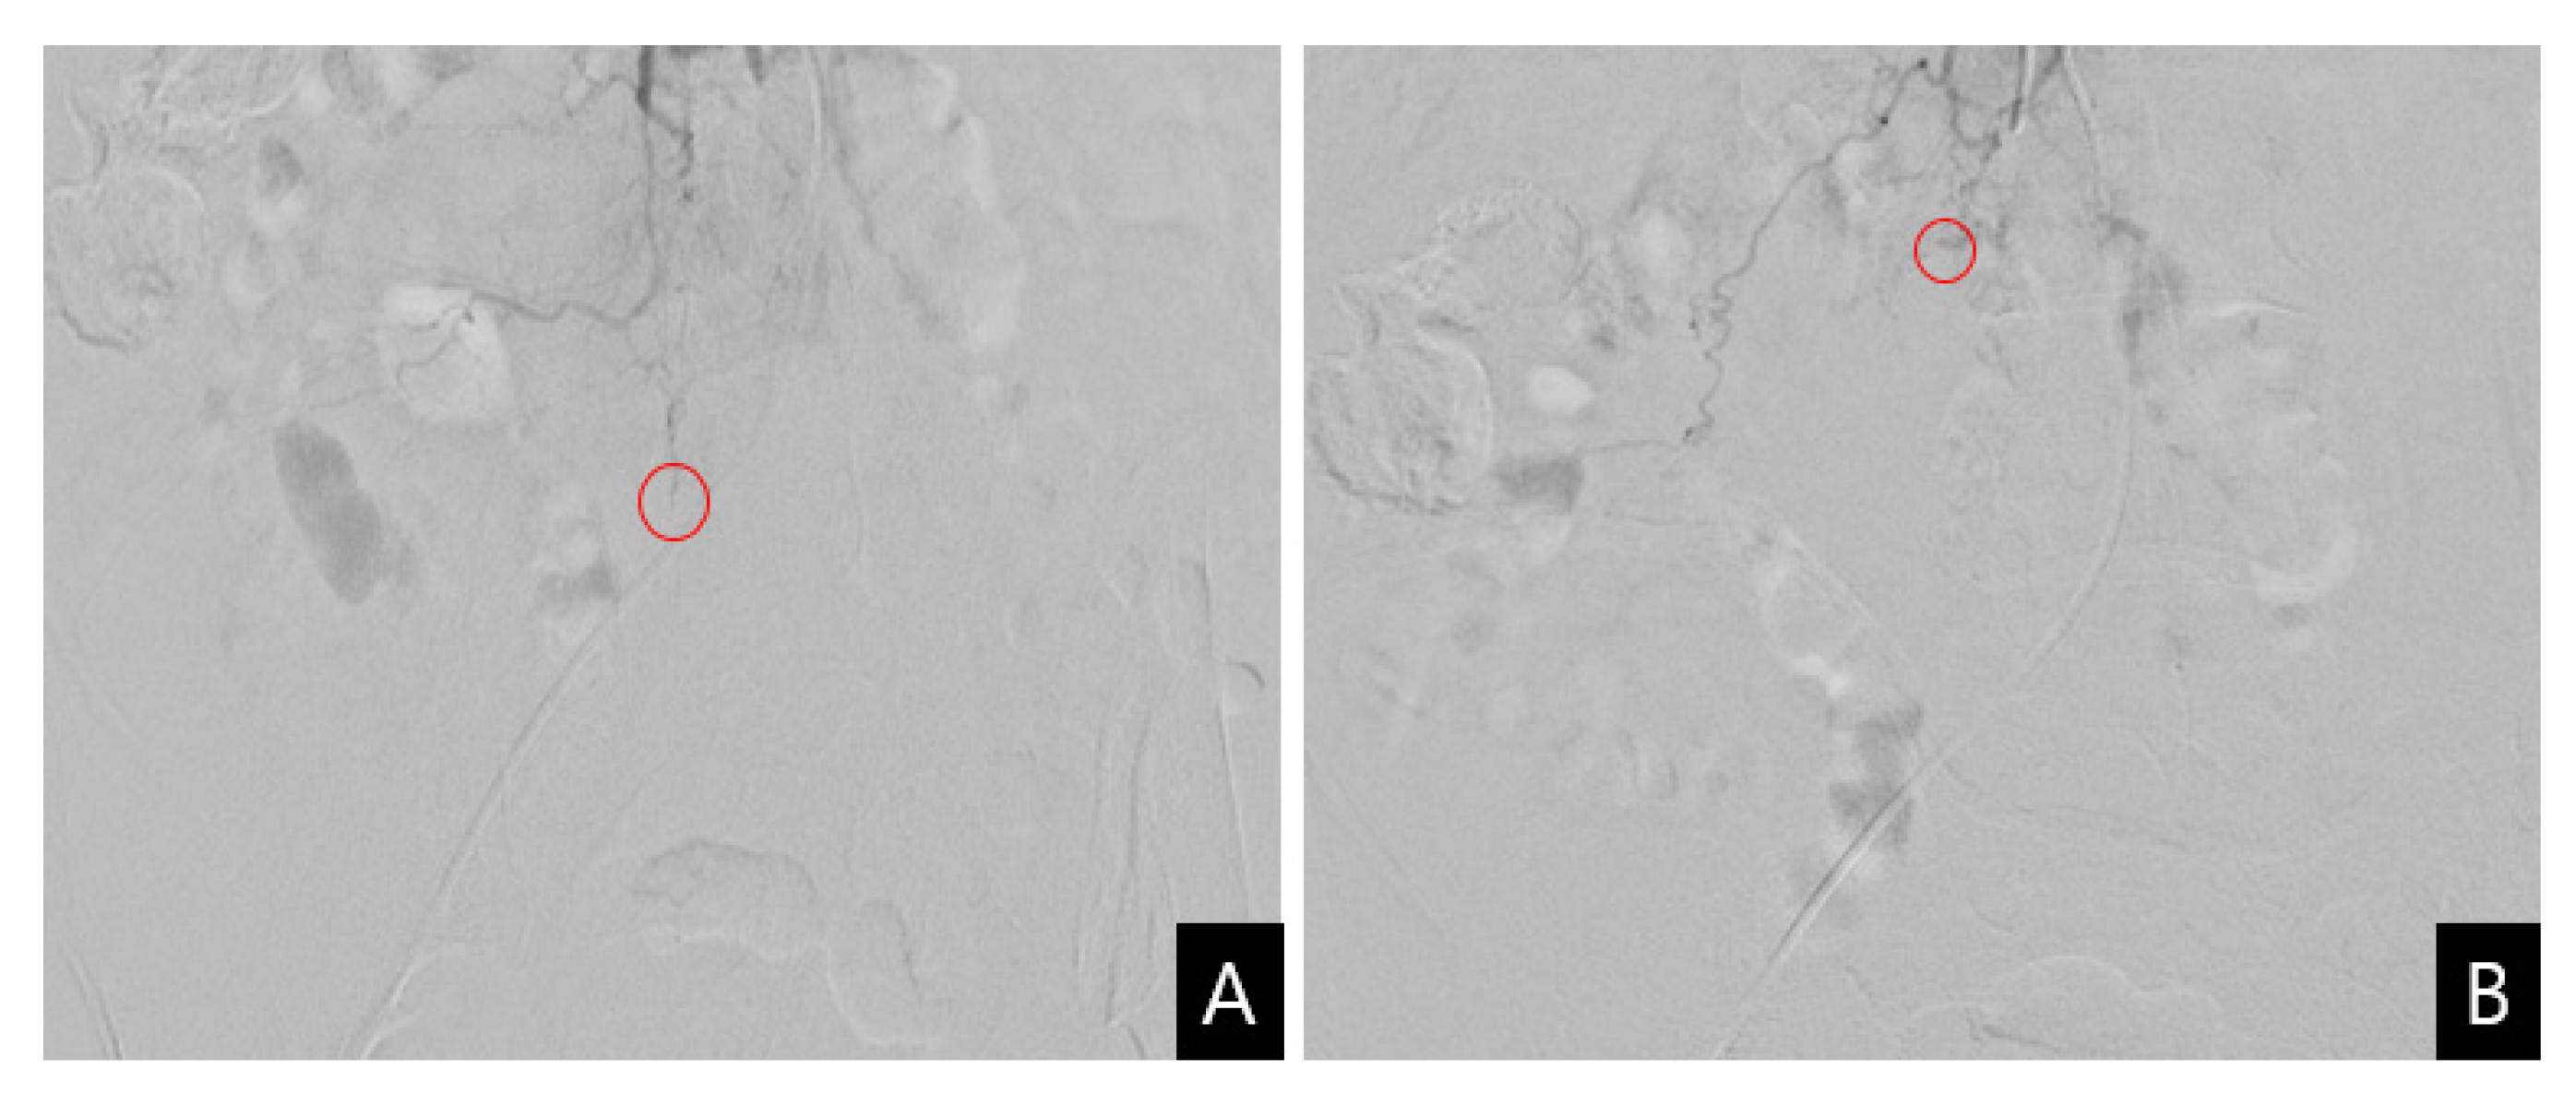

Figure 3.

Transcatheter arterial embolization. (A) Selective angiography reveals the slightly extravasated contrast medium (circle) from the distal fine branch of the right third lumbar artery; (B) Embolization of the suspicious bleeding vessel is performed using Gelfoam particles (circle).